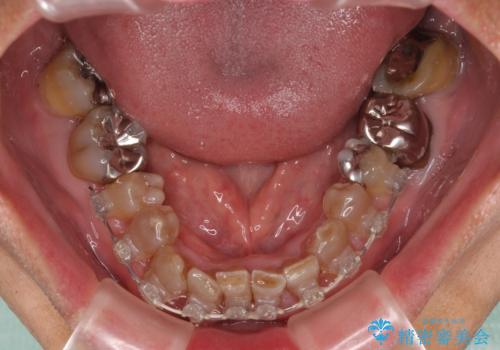

上下ともに前歯のセラミッククラウンによる補綴治療を希望されていましたが、下顎前歯は叢生が強いため、補綴治療前に部分矯正を行って歯列を整えた上で、補綴治療を行うこととしました。